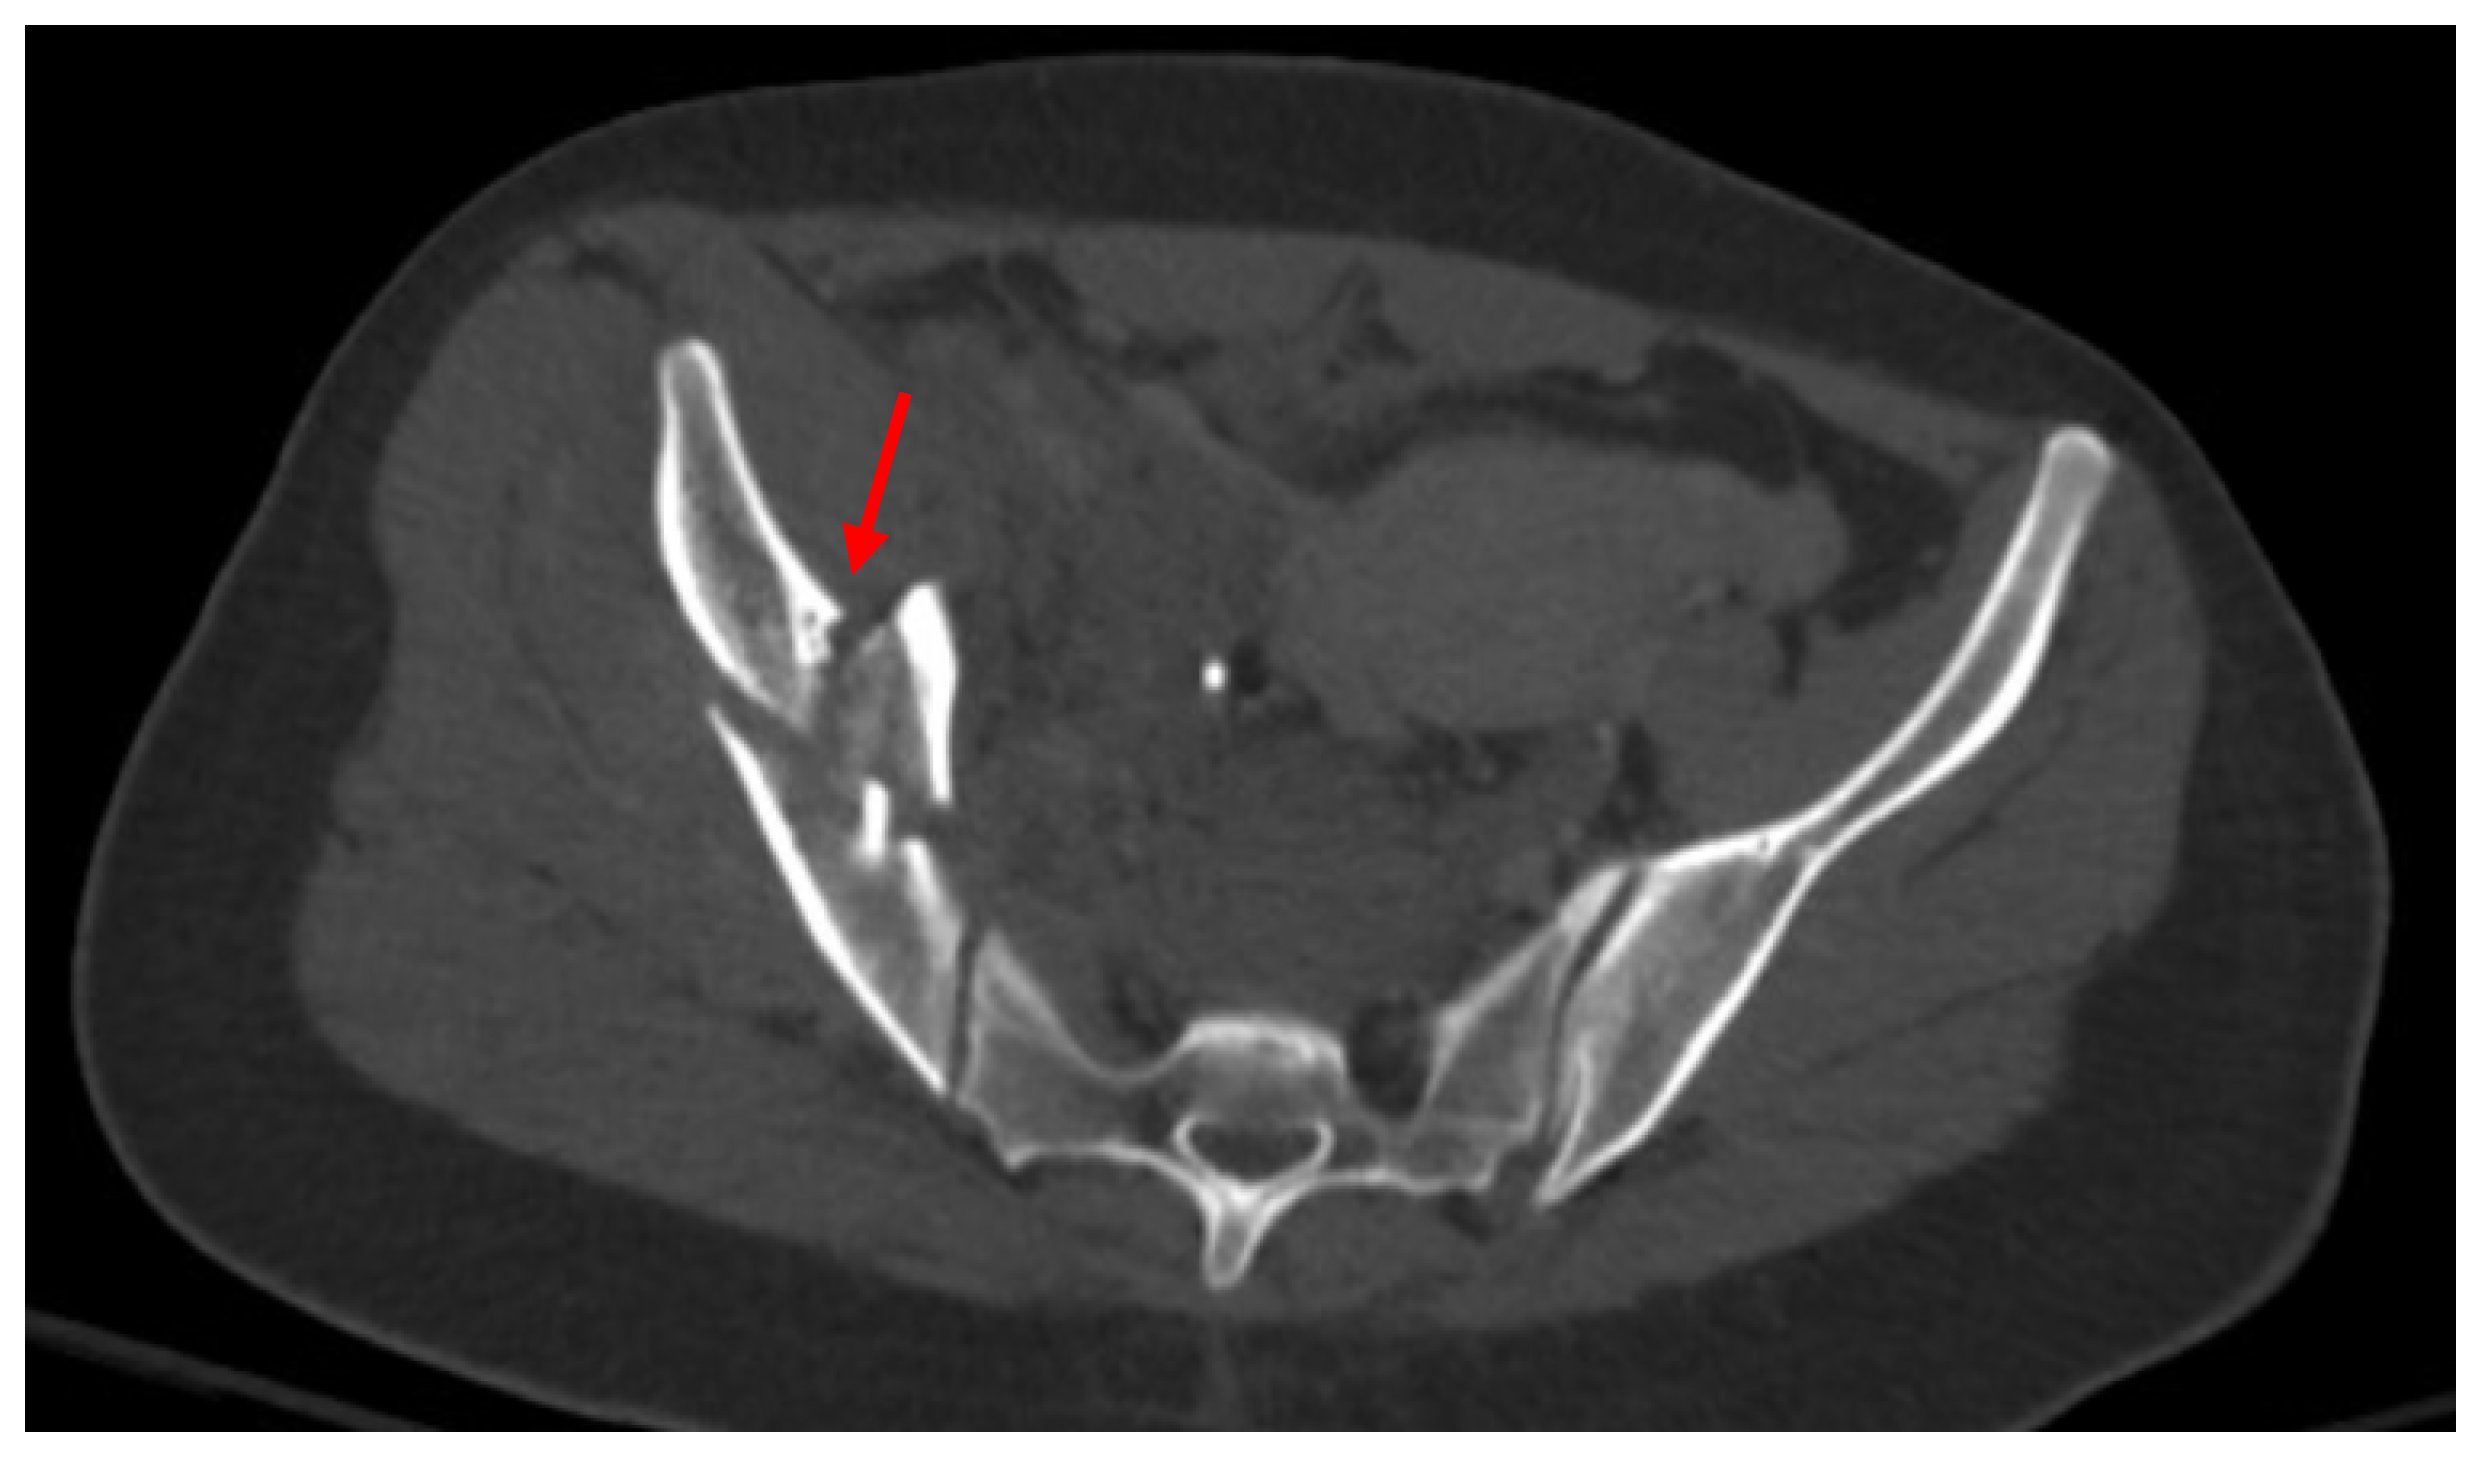

Pelvic imaging showed a fracture of the distal portion of the sacrum with anterior displacement, a comminuted fracture through the right iliac bone with moderate displacement, a moderately displaced fracture through the right inferior pubic ramus, and mildly displaced fractures of the right anterior and posterior acetabulum that involve the articular surface. There is a hemorrhage surrounding the right iliac fracture, a small volume hemorrhage in the right pelvic sidewall and the presacral space, and a small volume hemorrhage surrounding the urinary bladder (Figure 3).

Figure 3. CT abdomen/pelvis images of the described fractures in case 3. Red arrows are used to indicate the location of pelvic fractures for easier identification.